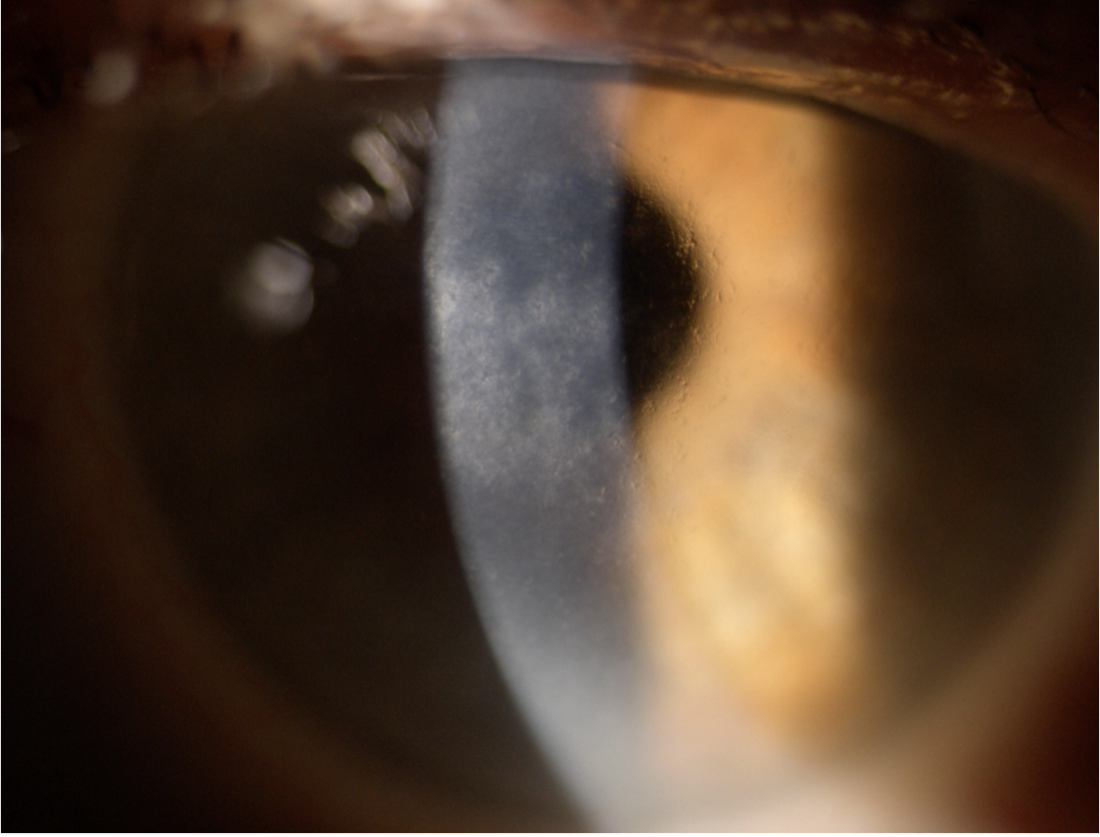

양안의 각막 기질 표층부에 격자형의 가치진 모양의 선이 발생합니다.

그리고 소결정의 혼탁이 발생하면서, 점점 격자 형태가 갖추어집니다.

이러면서 이러한 각막 혼탁이 상피층 아래에 위치하기 때문에, 각막 상피의 진무름이 일직 발생합니다.

각막의 중심부를 주로 침범하며, 주변부는 침범하지 않는 것이 특징입니다.